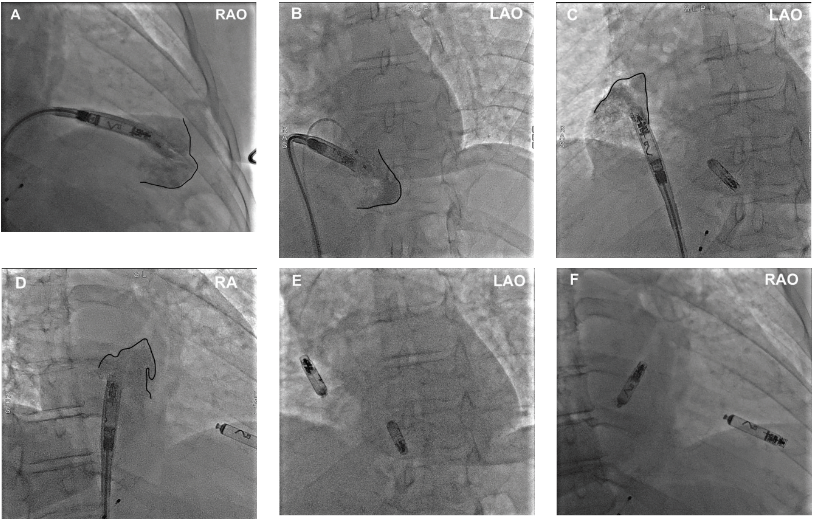

Case 2. A 77-year-old female presented with symptomatic high-degree AV block in the setting of hyperkalemia and underwent temporary transvenous pacing. Once the hyperkalemia was corrected, the patient did not appear to demonstrate any further pacing requirements, and the temporary transvenous pacemaker was removed. Over the next 24 hours, she developed intermittent episodes of high-degree AV block despite normalized potassium levels and without other reversible causes. The patient underwent Micra AV2 implant (Figure 2).

Li et al. Right Ventriculography Improves the Accuracy of Leadless Pacemaker Implantation in Right Ventricular Mid-septum. Reproduced with permission under CC BY 4.0. creativecommons.org/licenses/by/4.0/.15